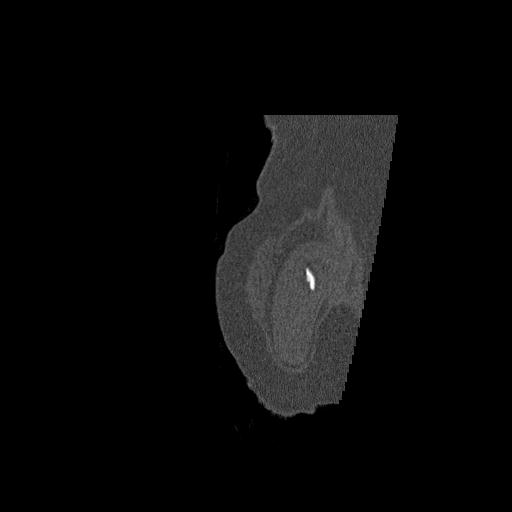

110286 2/17 股関節 2R 74歳女性 右人工骨頭

82084 1/14 1/20 股関節 2R 78歳男性 右人工骨頭

102811 1/13 股関節 2R 1/19 2R 80歳女性 右DHS